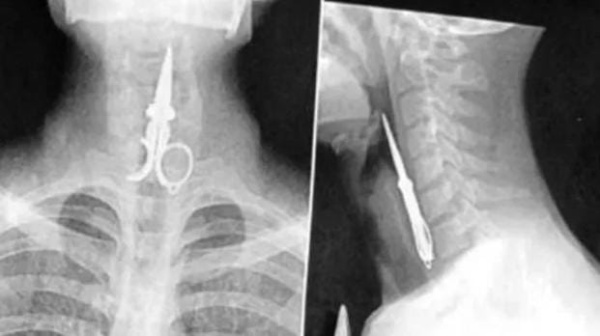

Un preso se tragó una tijera en modo de protesta y tuvieron que internarlo de urgencia

En 2021 el recluso se había cosido la boca para expresar “su descontento por la condena"